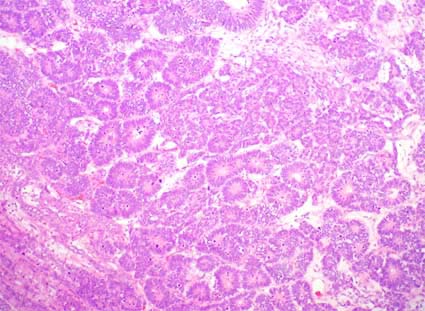

Figura 32. Tumor de Wilms en el que se identifican dos componente: epitelial, formando túbulos o con aspecto en "seudorrosetas" (o "pseudotúbulos"), y blastemal: células con poco citoplasma, densamente agrupadas, sin diferenciación. (H&E, X200)

Figura 33. Componente epitelial de tumor de Wlms; es el mismo caso de la figura 30. Aquí vemos el aspecto "rosetoide" más detallado. El componente epitelial es muy variable, puede haber túbulos primitivos o bien diferenciados, estructuras glomeruloides y otros aspectos que recuerdan elementos epiteliales primitivos. (H&E, X100)